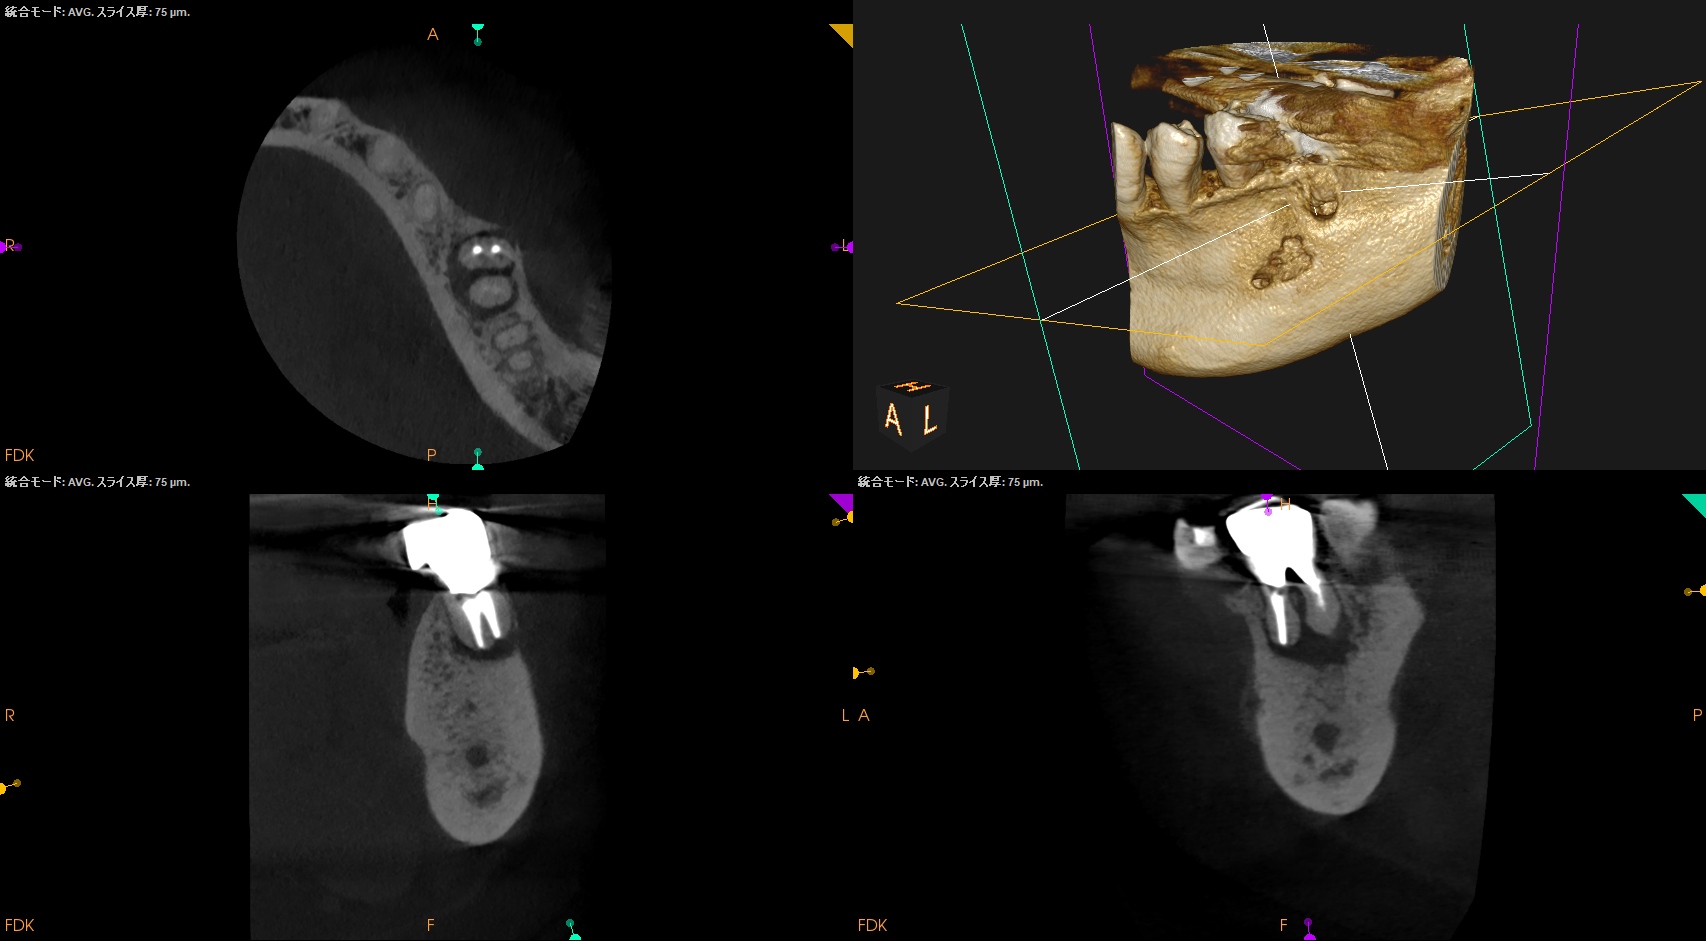

以下のようにPA,CBCTはなった。

M

D

術前・術直後と比較した。

90%がた治癒していると言えるだろう。